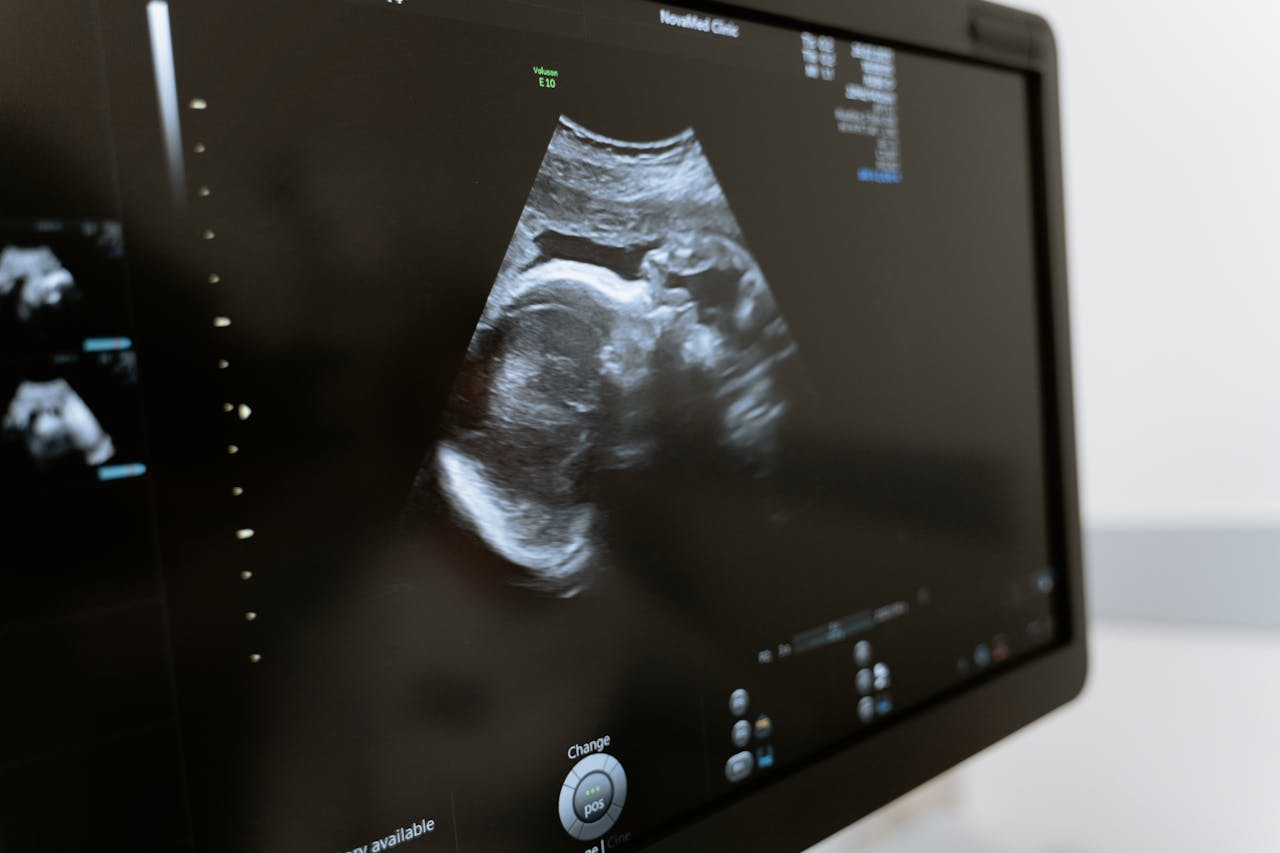

Testy przesiewowe są całkowicie bezpieczne i pozwalają oszacować prawdopodobieństwo choroby, choć nie dają stuprocentowej pewności. Pierwszym filarem diagnostyki jest badanie ultrasonograficzne (USG). W I trymestrze, między 11. a 14. tygodniem ciąży, wykonuje się tzw. USG genetyczne, podczas którego lekarz mierzy przezierność karkową płodu (NT) oraz ocenia obecność kości nosowej. Zwiększona NT (>2,5 mm) lub brak kości nosowej mogą sugerować aberracje chromosomowe. W kolejnych trymestrach ultrasonografia umożliwia dokładną ocenę anatomii dziecka, w tym serca, mózgu i narządów jamy brzusznej.